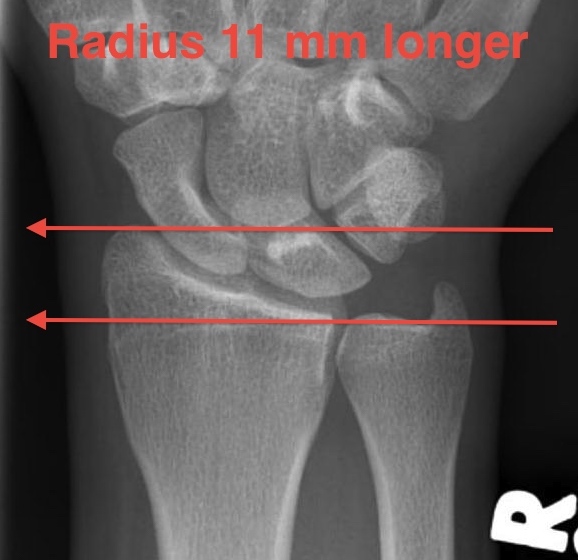

Distal Radius Angles

- radial volar tilt 11°

- radial inclination  22°

- radius is 11 mm longer than ulna

- ulna variance 2mm positive on average

Distal Radius NormalNormal Radial InclinationNormal Radial Length